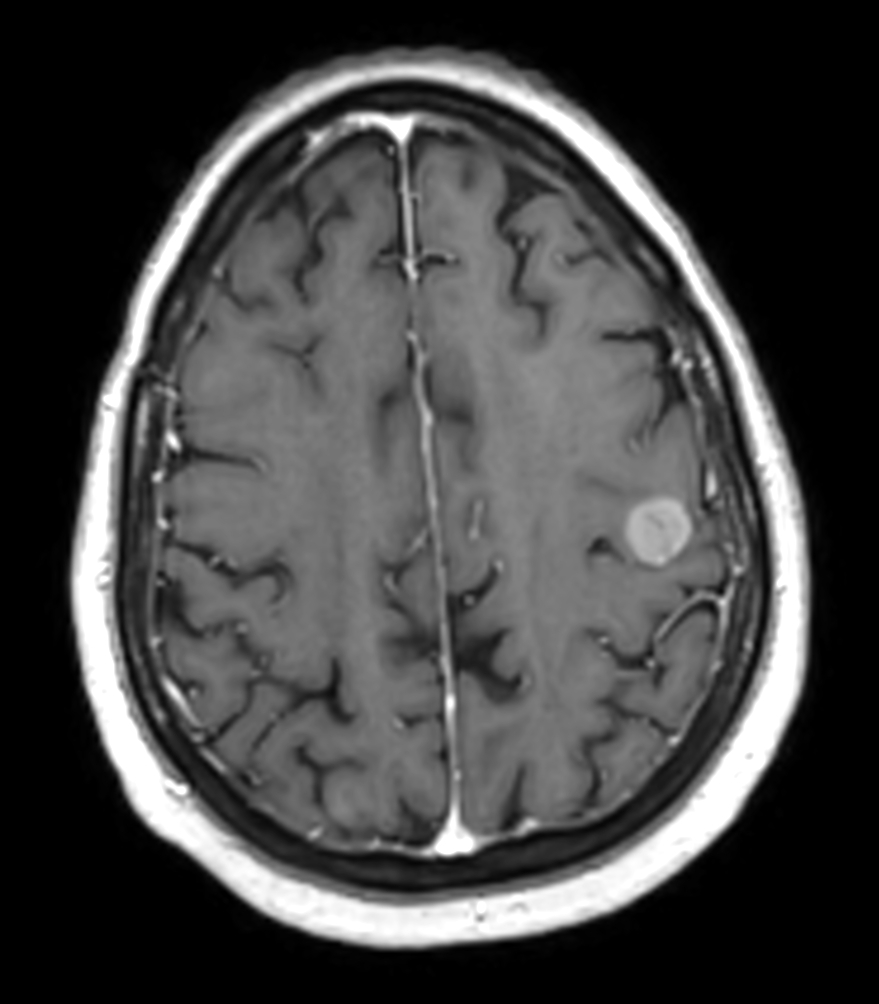

Female with one metastasis of pulmonary cancer underwent MRI simulation in the radiotherapy positioning mask on Ingenia MR-RT 1.5T before stereotactic radiation therapy with 25 Gy in 3 fractions.

Axial 3D T1w FFE pre contrast